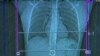

Las mamografías son radiografías de mama que pueden revelar tumores que son demasiado pequeños para percibirse al tacto, pero también plantean muchas falsas alarmas, que han derivado en preocupaciones, gastos y tratamientos innecesarios, lo que puede haber alejado a este colectivo.